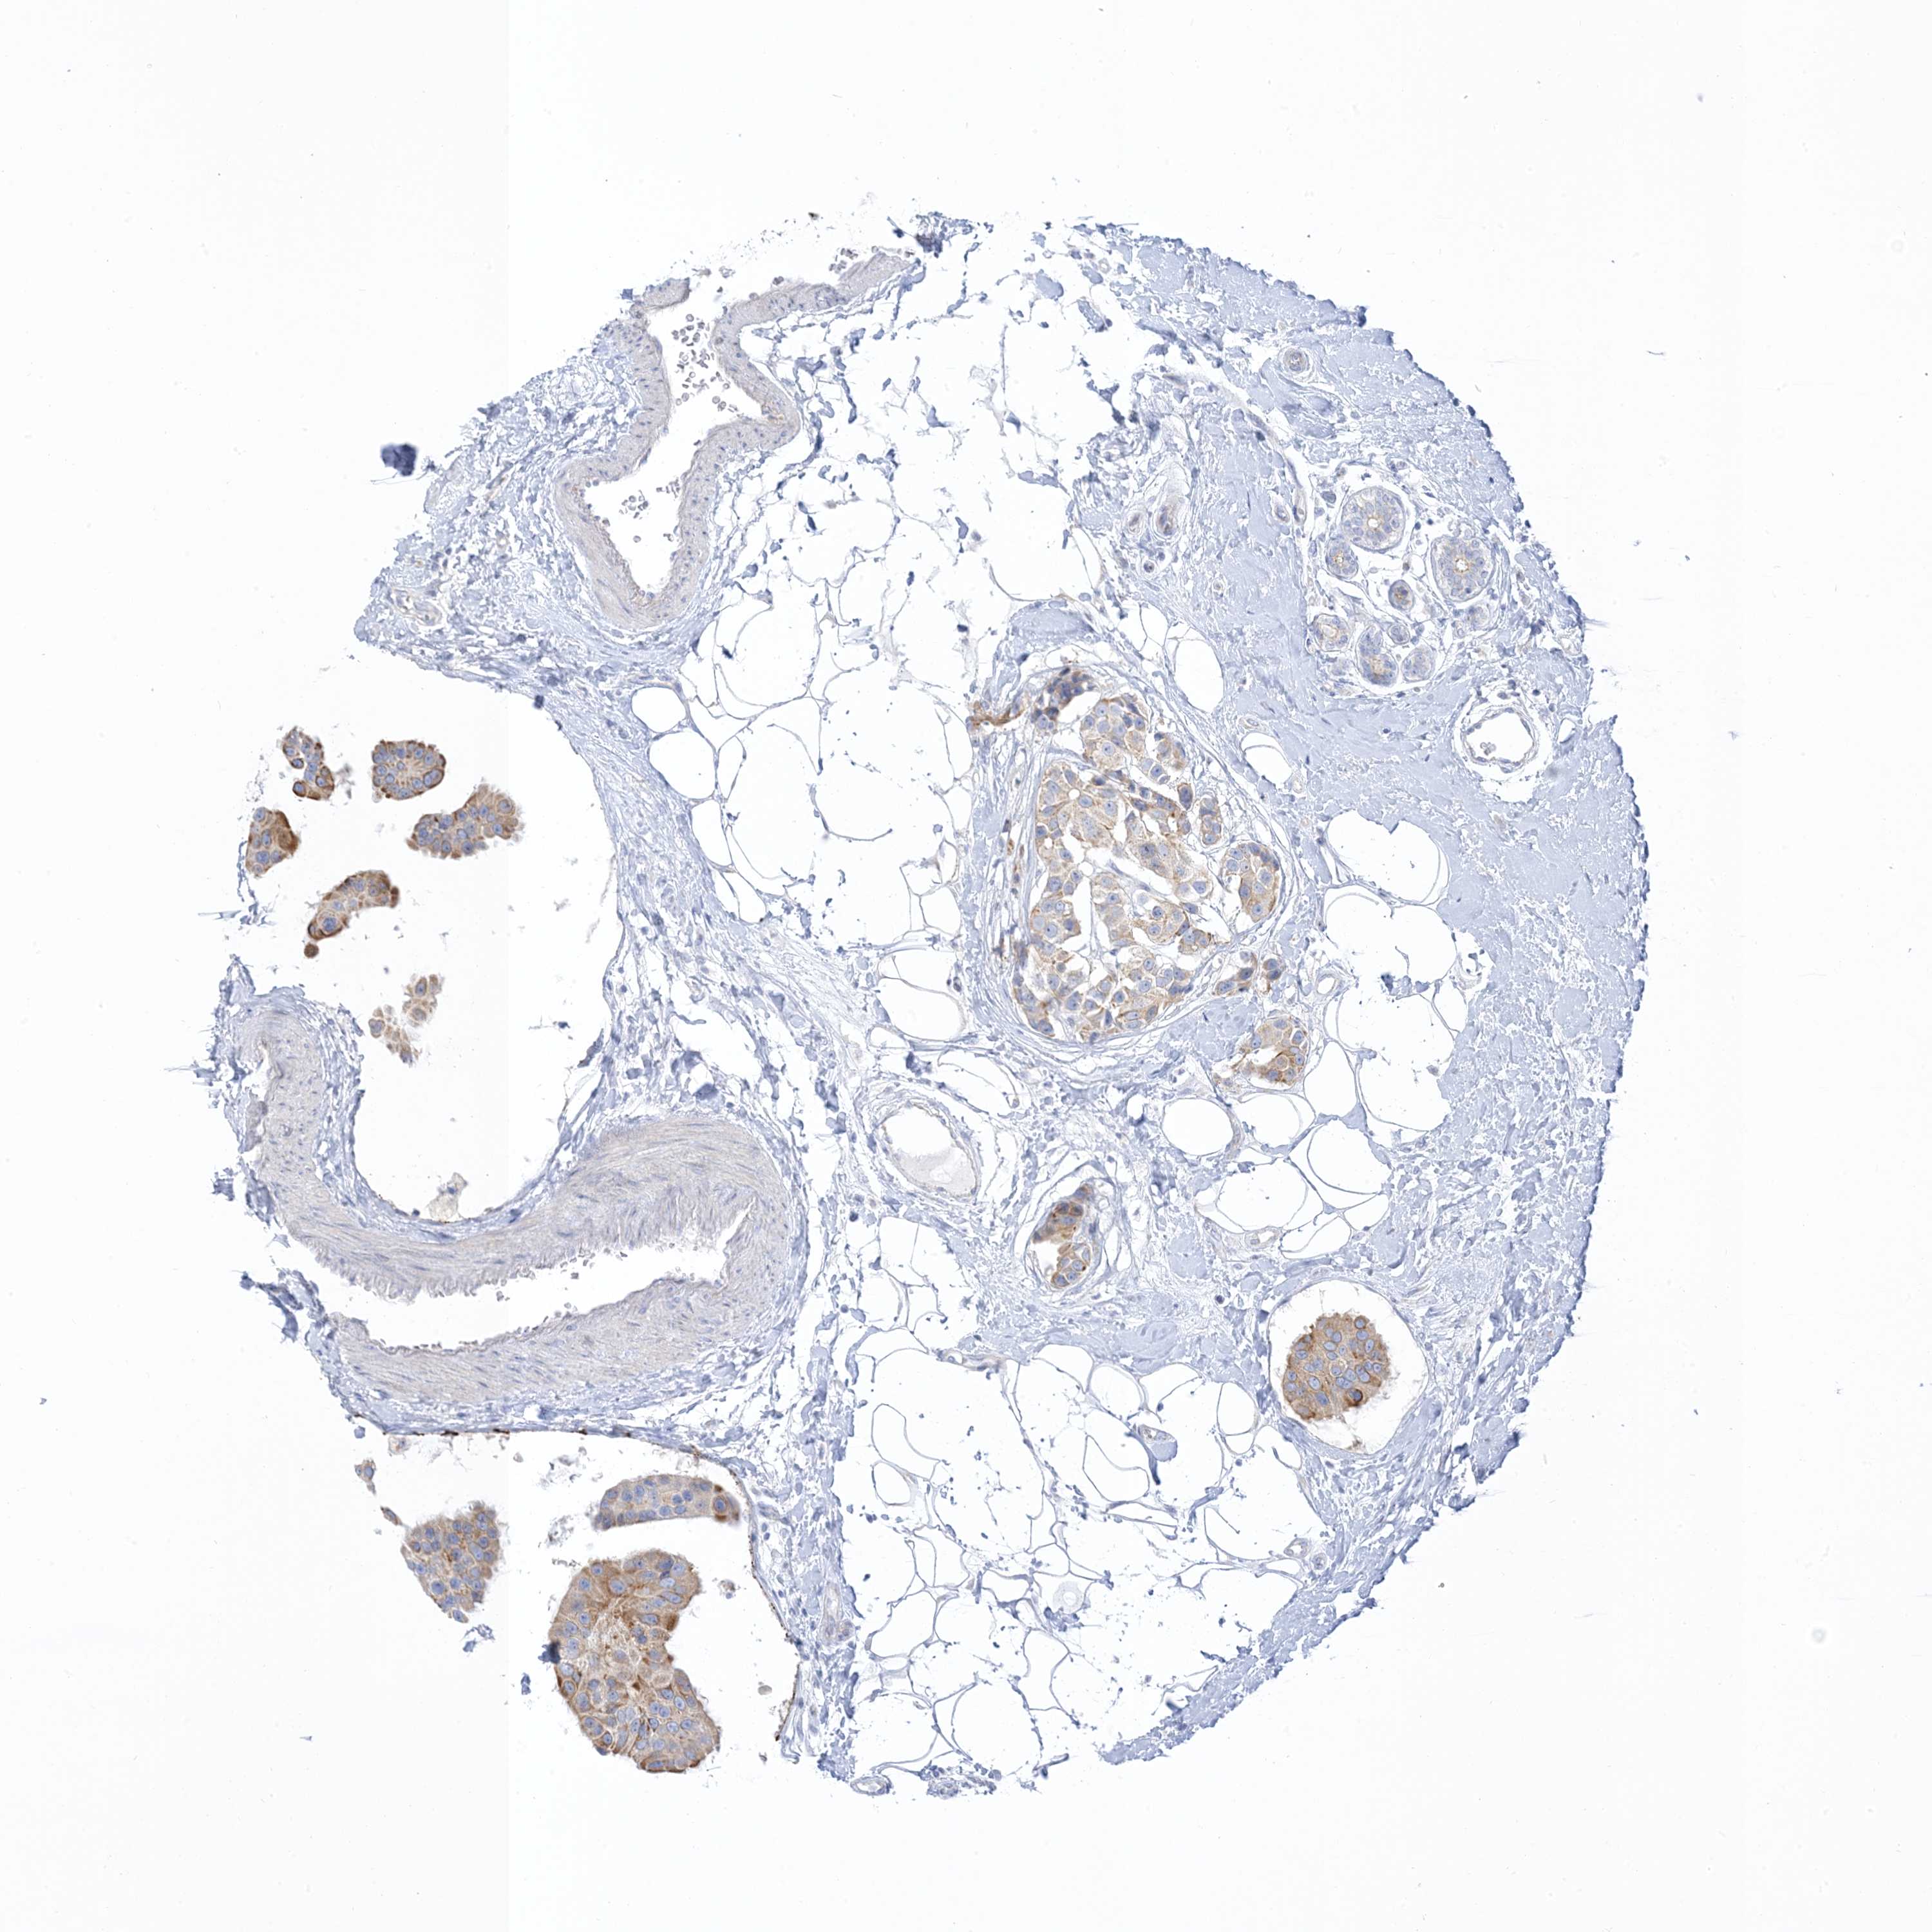

BRCA TCGA BRCA VALIDATION PROTEIN EXPRESSION